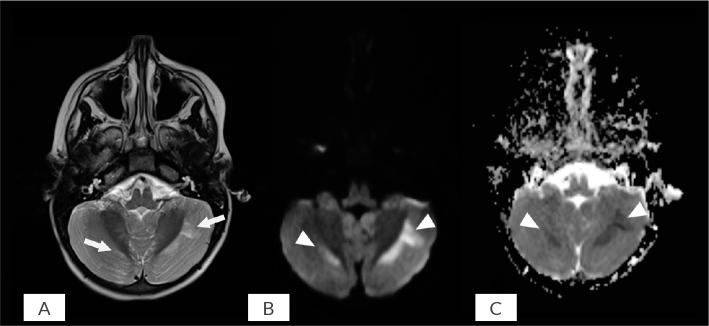

Anti-N-methyl-D-aspartate receptor (anti-NMDAR) encephalitis is a rare but increasingly recognized autoimmune disorder that predominantly affects adolescents and young adults. It often presents with prominent psychiatric symptoms at onset, leading to frequent misdiagnosis as a primary psychiatric disorder. We report the case of a 16-year-old girl who presented with acute psychiatric symptoms, including mood lability, hallucinations, and aggression, initially diagnosed as first-episode psychosis. Her condition rapidly deteriorated under antipsychotic treatment, progressing to neuroleptic malignant syndrome, followed by the emergence of cerebellar ataxia, which raised strong suspicion of an underlying organic aetiology. Subsequent investigations confirmed the diagnosis of anti-NMDAR encephalitis. The patient was successfully treated with intravenous immunoglobulin, achieving complete recovery. This case underscores the diagnostic challenges posed by isolated psychiatric presentations of anti-NMDAR encephalitis in adolescents. Early recognition and prompt initiation of immunotherapy are crucial for favourable outcomes, particularly in cases presenting with antipsychotic intolerance or atypical clinical progression.

Learning points: Anti-N-methyl-D-aspartate receptor encephalitis can initially present as an isolated psychiatric syndrome mimicking primary psychosis, particularly in adolescents, often leading to misdiagnosis.The development of neuroleptic malignant syndrome during a first-episode psychosis, occurring rapidly and at low antipsychotic doses, should raise suspicion of an organic aetiology, notably autoimmune encephalitis.Magnetic resonance imaging, electroencephalogram, and cerebrospinal fluid analysis are essential to distinguish autoimmune encephalitis from primary psychiatric disorders.